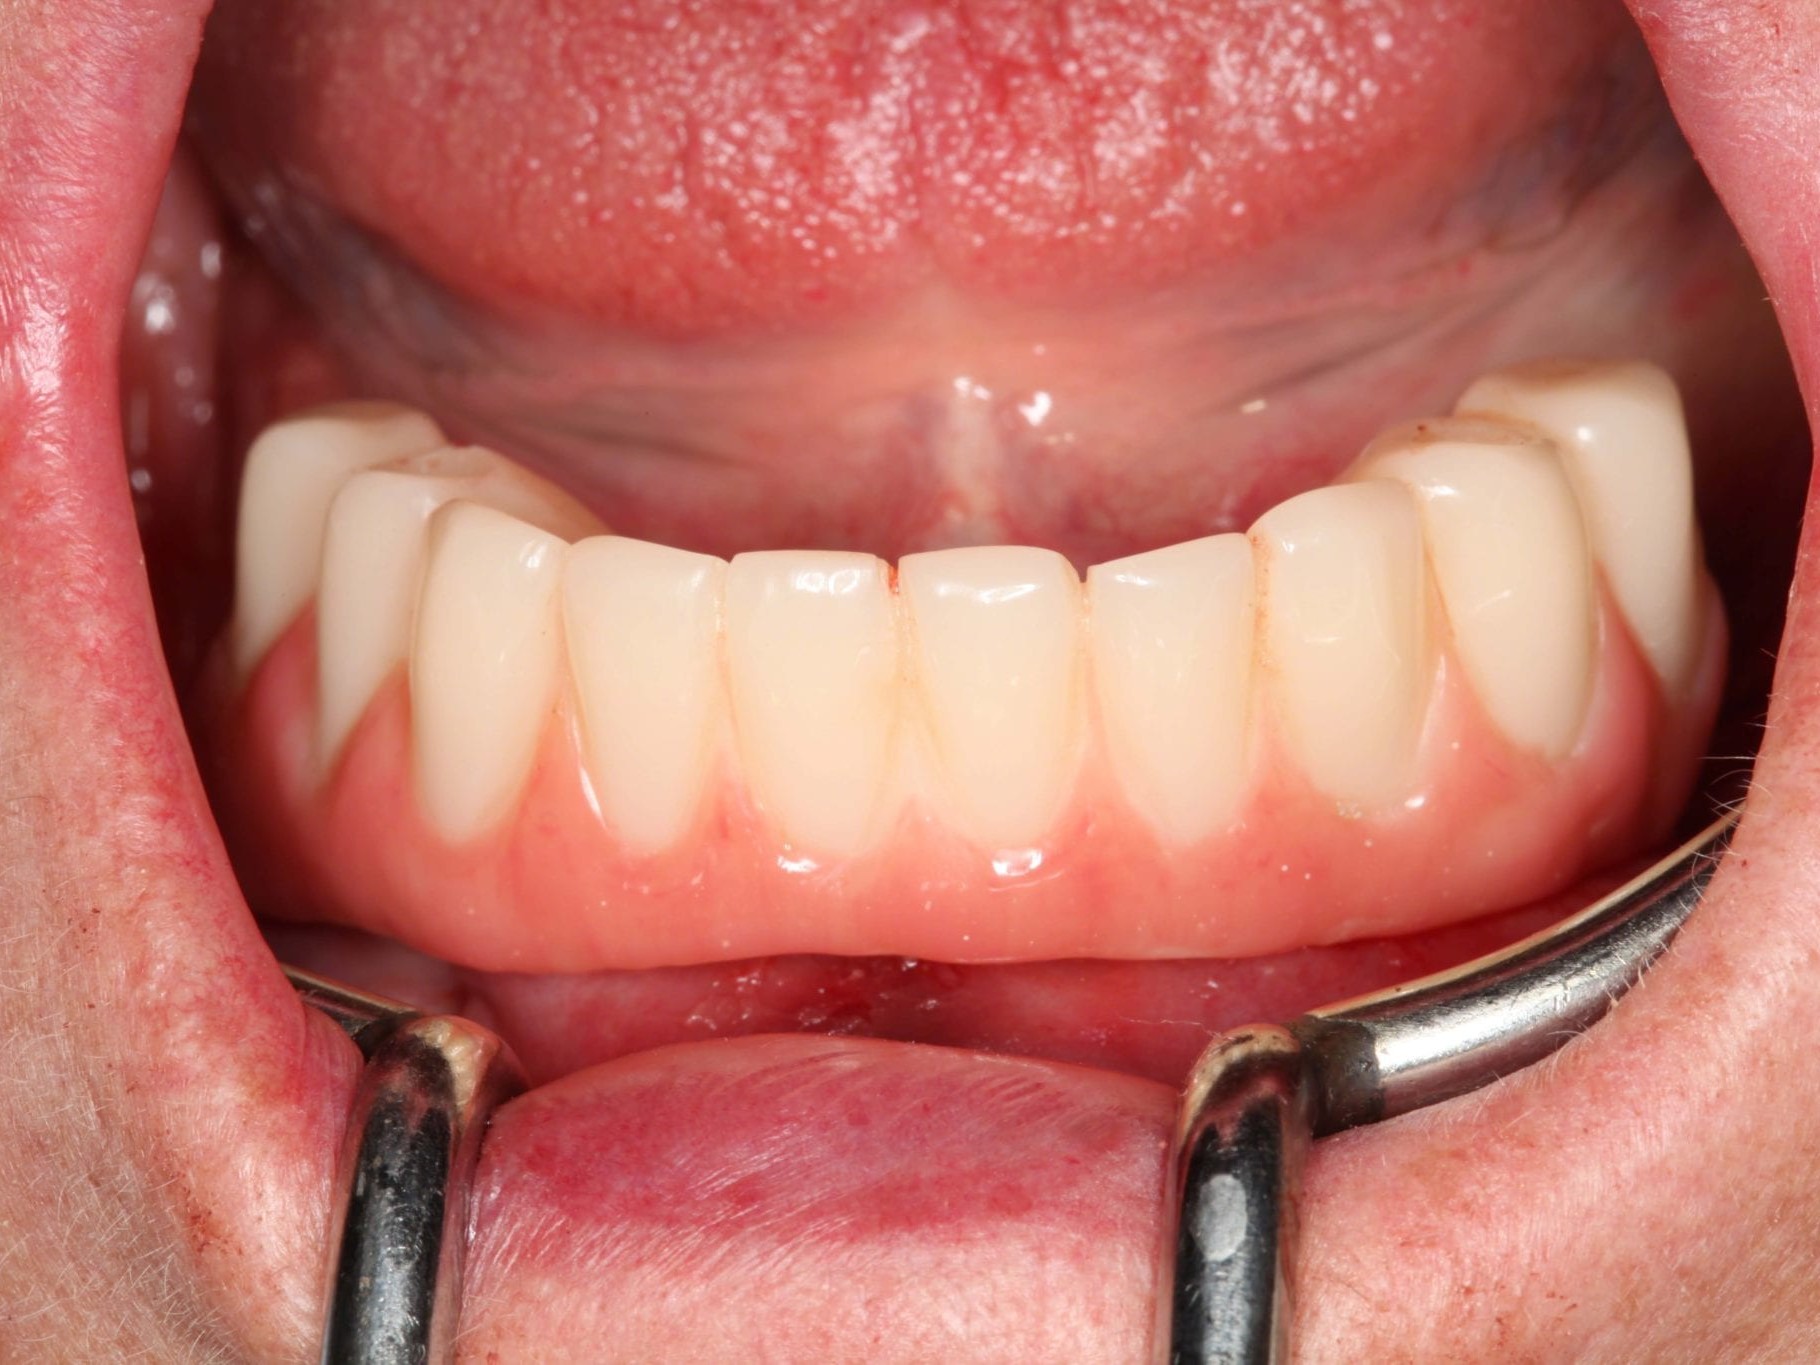

In Lokalanästhesie unter anästhesiologischem Standby mit intravenöser Antibiose mittels Clindamycin 600 mg 2mal/d wurde die Bohrschablone eingesetzt und mit Osteosyntheseschrauben fixiert (Abb. 8). Der Eingriff erfolgte nahezu flapless und somit transgingival. Nun erfolgte die Umsetzung des Straumann Hülse-in-Hülse-Konzeptes. Der Zylinder des Bohrlöffels wird in die an der Bohrschablone fixierten Hülse (Ø 5 mm) in den geplanten Regionen eingeführt. Für jeden Bohrerdurchmesser (Ø 2,2 mm und Ø 2,8 mm) ist ein entsprechender Bohrlöffel erhältlich. Jeder Bohrlöffel besitzt an seinen Enden Zylinder unterschiedlicher Höhe, die entsprechend chirurgischem Protokoll angewendet werden. Es wurden sämtliche Bohrstollen protokollgemäß aufbereitet (Abb. 9-11). Nach der Aufbereitung der Bohrstollen für die angulierten Implantate (Abb. 12-14) wurden die Straumann Bone Level Tapered Implantate (ø 3,3 mm) in regio 035 (Länge 10 mm) und 045 (Länge 12) gesetzt (Abb. 15). Abschließend wurden sämtliche Endpositionen der Implantate in regio 035 und 045 anhand der Lasermarkierungen am Übertragungsteil betreffend ihrer orovestibulären Ausrichtung exakt überprüft (Abb. 16). Nach Entfernung der Einbringhilfen und der Osteosyntheseschrauben konnte die Bohrschablone wieder entnommen werden. In regio 032 und 042 wurden nun die durchmesserreduzierten Straumann NNC (ø 3,3 mm Länge 12 mm) Implantate inseriert (Abb. 17, 18). Bei diesen Implantaten bedurfte es keiner Ausrichtung bezogen auf die orofasziale Ausrichtung. Hier musste die Insertionstiefe bezogen auf das NNC-Implantat beachtet werden (Abb. 19). Die NNC-Implantate wurden mit den entsprechenden Klebebasen versehen (Abb. 20). Danach wurden in regio 035 und 045 auf die Pro Arch Sekundärteile die dazugehörigen Retentionskappen (Abb. 21), die zur Vergrößerung der Oberfläche mit 120 μ Aluminiumoxyd abgestrahlt wurden, eingesetzt. Es erfolgte der typische Naht-Wund-Verschluss mit Einzelknopfnähten. Zum Abschluss erfolgte das prothetische Procedere mit der Eingliederung des Interimszahnersatzes in Okklusion (Abb. 22). Hierfür wurden die Retentionskappen und die Klebebasen mit dem Sofortprovisorium über ein selbsthärtendes fluoreszierendes kaltpolymerisierendes Paste-Paste-Kartuschensystem fixiert, dieser Zahnersatz extraoral versäubert (Abb. 23) und in der Mundhöhle refixiert (Abb. 24). Die Schraubenkanäle wurden mit Kunststoff verschlossen (Abb. 25). Abschließend erfolgte die radiologische Kontrolluntersuchung (Abb. 26).